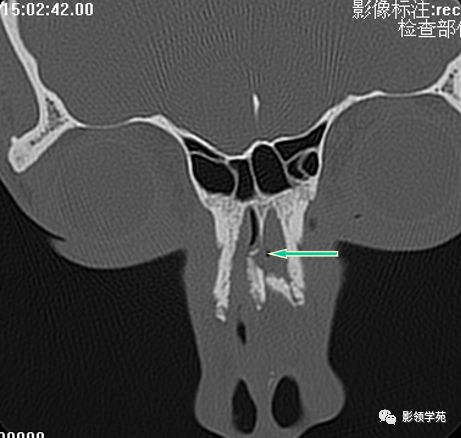

鼻骨冠状面HRCT

左侧鼻骨线形骨折

左上颌骨额突骨折

双侧上颌骨额突骨折